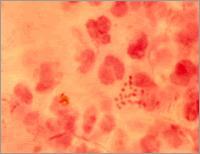

1.形態與染色 革蘭陰性雙球菌,與腦膜炎球菌相似,兩菌接觸面平坦,形似一對咖啡豆。在濃汁標本中,急性淋病患者的細菌大多位於中性粒細胞內,而慢性患者則多在細胞外。無芽胞和鞭毛,一般無莢膜,有菌毛。

1.直接鏡檢 去泌尿生殖道分泌物塗片,革蘭染色鏡檢,發現中性粒細胞內有革蘭陰性雙球菌,有診斷價值,但要注意與這些部位寄居的其它非致病性奈氏菌相鑑別。此法對急性病人檢出率高,而慢性病人檢出率低。